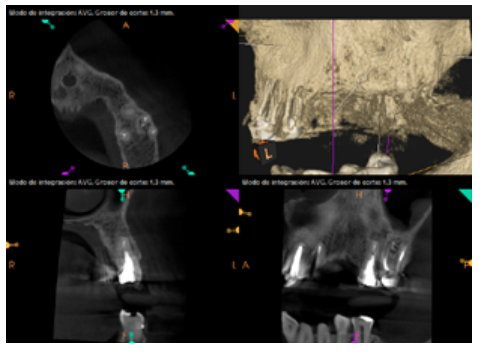

To confirm the endodontic origin and the size of the lesions, tomographic examinations were performed with a slice thickness of 75 microns using CBCT CS8100 (Carestream Dental™), in which radiolucent periapical lesions were observed at the level of 12, 11, 21 (with bicortical involvement), 25 and vestibular roots at 26 (Figures 4 to 8).

Meanwhile, the vestibular roots of 26 showed clearly deficient root canal treatment, being underextended by several millimetres, as well as an omitted mesiopalatine canal (MP). Therefore, the need to repair the root canal treatment was proposed to the patient before performing microsurgery on tooth 25 (Figure 9).

Subsequently, the canals of the buccal roots of 26 were retreated, performing a coronal access through the crown, eliminating part of the cast stump, locating the omitted MP canal and unobturating the mesiobuccal (MB) and distobuccal (DB). Once these canals were disinfected and shaped, they were filled with bioceramic sealing cement (BioRoot RCSTM, Septodont) and guttapercha.

Six months later, the patient went for a check-up without any symptoms, both anteriorly and posteriorly. Periapical radiographs showed a decrease in the size of the pre-existing radiolucent periapical lesions (Figures 10 and 11). Given that the lesion on 25 remained to be treated, a control CBCT was performed where improvement at the level of 26 was verified (Figure 12), so microsurgery on 25 was scheduled.

The intracanal posts in the single-root teeth in our case, whose removal would have entailed the sacrifice of the scarce remaining tooth that could remain under the metal ceramic crowns, made us opt for periapical surgery on these teeth. However, tooth 26 was underfilled by several millimetres in the buccal roots and the CBCT showed an omitted MP canal, so we opted for nonsurgical root canal retreatment in this tooth.